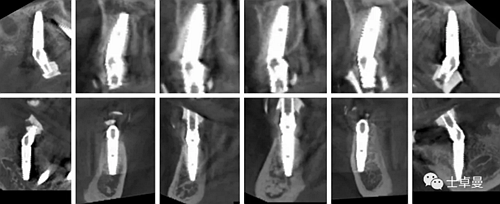

影像學檢查

CBCT檢查:顯示口內(nèi)余留牙牙槽骨吸收至根尖1/3;

上頜雙側后牙區(qū)上頜竇底可用骨高度不足;

下頜雙側后牙區(qū)下頜神經(jīng)管上方可用骨高度不足。

手術完成后復查CBCT與術前設計對比,驗證植入精度。